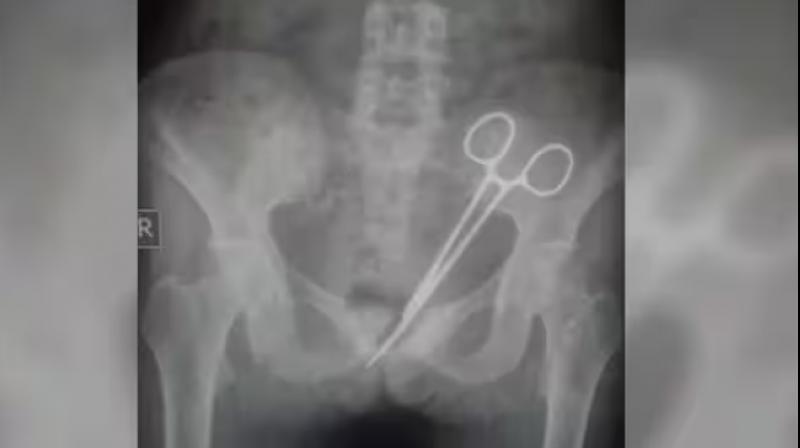

ਗੰਗਟੋਕ : ਗੰਗਟੋਕ ਦੇ ਐਸ.ਟੀ.ਐਨ.ਐਮ. ਹਸਪਤਾਲ ਦੇ ਡਾਕਟਰਾਂ ਨੇ ਇਕ ਔਰਤ ਦੇ ਪੇਟ ’ਚ 12 ਸਾਲਾਂ ਤੋਂ ਪਈ ਕੈਂਚੀ ਨੂੰ ਬਾਹਰ ਕਢਿਆ ਜੋ ਸਰਜਰੀ ਦੌਰਾਨ ਉਸ ਦੇ ਪੇਟ ’ਚ ਹੀ ਰਹਿ ਗਈ ਸੀ। ਇਕ ਅਧਿਕਾਰੀ ਨੇ ਸਨਿਚਰਵਾਰ ਨੂੰ ਇਹ ਜਾਣਕਾਰੀ ਦਿਤੀ।

ਅਧਿਕਾਰੀ ਨੇ ਦਸਿਆ ਕਿ 12 ਸਾਲ ਪਹਿਲਾਂ ਐਸ.ਟੀ.ਐਨ.ਐਮ. ਹਸਪਤਾਲ ’ਚ ਔਰਤ ਨੇ ਅਪਣੇ ਅਪੈਂਡਿਕਸ ਦਾ ਆਪਰੇਸ਼ਨ ਕਰਵਾਇਆ ਸੀ ਜਿਸ ਦੌਰਾਨ ਉਸ ਦੇ ਪੇਟ ’ਚ ਕੈਂਚੀ ਛੱਡ ਦਿਤੀ ਗਈ ਸੀ।

ਅਪੈਂਡਿਕਸ ਦੇ ਆਪਰੇਸ਼ਨ ਤੋਂ ਬਾਅਦ ਔਰਤ ਨੂੰ ਦਰਦ ਹੁੰਦਾ ਰਹਿੰਦਾ ਸੀ। ਉਸ ਦੇ ਪਰਵਾਰਕ ਜੀਅ ਉਸ ਨੂੰ ਐਸ.ਟੀ.ਐਨ.ਐਮ. ਹਸਪਤਾਲ ਲੈ ਕੇ ਆਏ। ਐਕਸ-ਰੇ ਨੇ ਉਸ ਦੇ ਪੇਟ ਵਿਚ ਕੈਂਚੀ ਪਾਈ। ਉਨ੍ਹਾਂ ਦਸਿਆ ਕਿ ਡਾਕਟਰਾਂ ਨੇ ਵੀਰਵਾਰ ਨੂੰ ਔਰਤ ਦੇ ਪੇਟ ’ਚੋਂ ਕੈਂਚੀ ਕੱਢਣ ਲਈ ਆਪ੍ਰੇਸ਼ਨ ਕੀਤਾ।